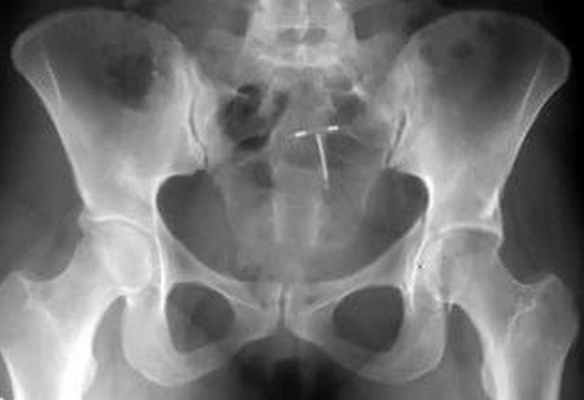

При поступлении пациента с травмой вертлужной впадины наличие у него вывиха в тазобедренном суставе являлось показанием к его экстренному вправлению с последующим наложением скелетного вытяжения или аппаратной фиксацией. Это является залогом успеха последующей реконструкции. Так, на рисунке 1 слева представлена рентгенограмма пациента с переломом задней колонны левой вертлужной впадины со смещением и вывихом бедра. Вправление вывиха бедра в экстренном порядке привело к репозиции перелома задней колонны вертлужной впадины (рис. 1 справа), что в дальнейшем облегчило выполнение остеосинтеза.

Рисунок 1. Рентгенограммы мужчины 32 лет. Автодорожная травма (удар в область левого колена при столкновении): слева – при поступлении, перелом задней колонны левой вертлужной впадины со смещением, вывих левого бедра; стрелка указывает на смещение фрагмента задней колонны; справа – после вправления вывиха в экстренном порядке наступила репозиция перелома; стрелка указывает отсутствие смещения